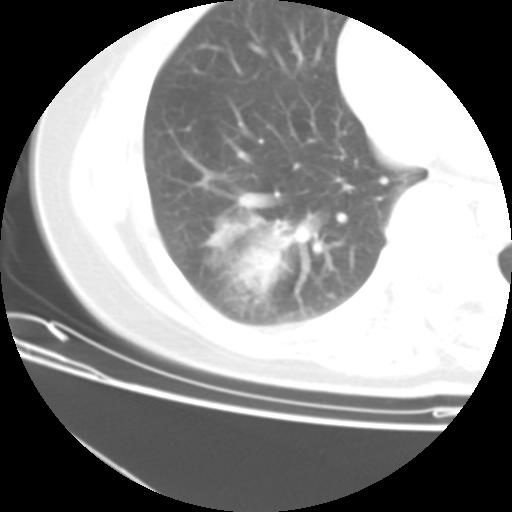

右肺下叶类癌

女 46岁,咳嗽咳血10月

【linyiming】右肺下叶见类圆形软组织影,边缘欠规整,略分叶状。考虑炎症假瘤可能?

未排除周围型肺癌。建议CT增强。

【心路寻觅】右肺下叶良性占位伴阻塞性肺炎,抗炎治疗后复查,不像单纯的炎性假瘤。

【aosangwa】肺癌的主要特征是:毛刺征、分叶征及胸膜凹陷征,此病例位于右肺下叶距胸膜很近,但没有胸膜凹陷征,其周围像示渗出性病变,病灶在两窗上没有大小没有发生大小改变。

考虑其良性肿瘤,炎性假瘤可能性大,其主要鉴别是:结核球、周围型肺癌、血管瘤

病理诊断类癌(周围型)。